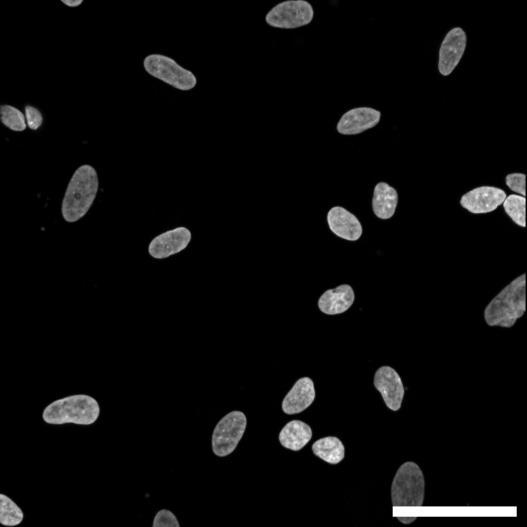

Fig 2 ACHP and Dexamethasone decrease TIC induced upregulation of GBP2 intensity and pro-inflammatory cytokines and growth factor release in hiPSC-derived astrocytes A) Representative images of hiPSC-derived astrocytes treated with Control or TIC and stained for the nucleus (DAPI, grey), Guanylate-binding protein 2 (GBP2, cyan or FIRE) and the astrocytic marker glial fibrillary acidic protein (GFAP, magenta) Z-stacks were acquired with a Zeiss LSM 880 confocal laser scanning microscope B) Quantification of the median GBP2 intensities in control and TIC stimulated cells Confocal images were acquired with an Opera Phenix High Content Screening System (PerkinElmer) and image analysis was done using Harmony 5 2 software Data presented as mean ± SEM for n = 3 biological replicates P-values generated by a two-way ANOVA with Dunnett post-test for multiple comparisons to Control+TIC P ≤ 0 05 (*), P ≤ 0 01 (**), P ≤ 0 001 (***), P ≤ 0 0001 (****) C) Representative confocal laser scanning microscope image of hiPSC-derived astrocytes indicate a change in morphology for GFAP (cyan) under TIC conditions D) Quantification of CXCL10, IL-6, YKL-40, CCL2, CCL5, GM-CSF and VCAM-1 secretion performed on astrocyte conditioned media using LUMINEX or ELISA N=3 P-values were generated by a One-way ANOVA with Dunnett post-test for multiple comparisons to Control+TIC Exception: P-value for YKL-40 (Control vs Control+TIC ) was calculated by unpaired t-test (mean±SEM) Abbreviation: Dexamethasone (Dex) E) Use of the NFkB reporter in astrocyte reactivity model Images were acquired and analysed using and Incucyte SX3 N=1; P-values were calculated by unpaired t-test (mean±SEM)